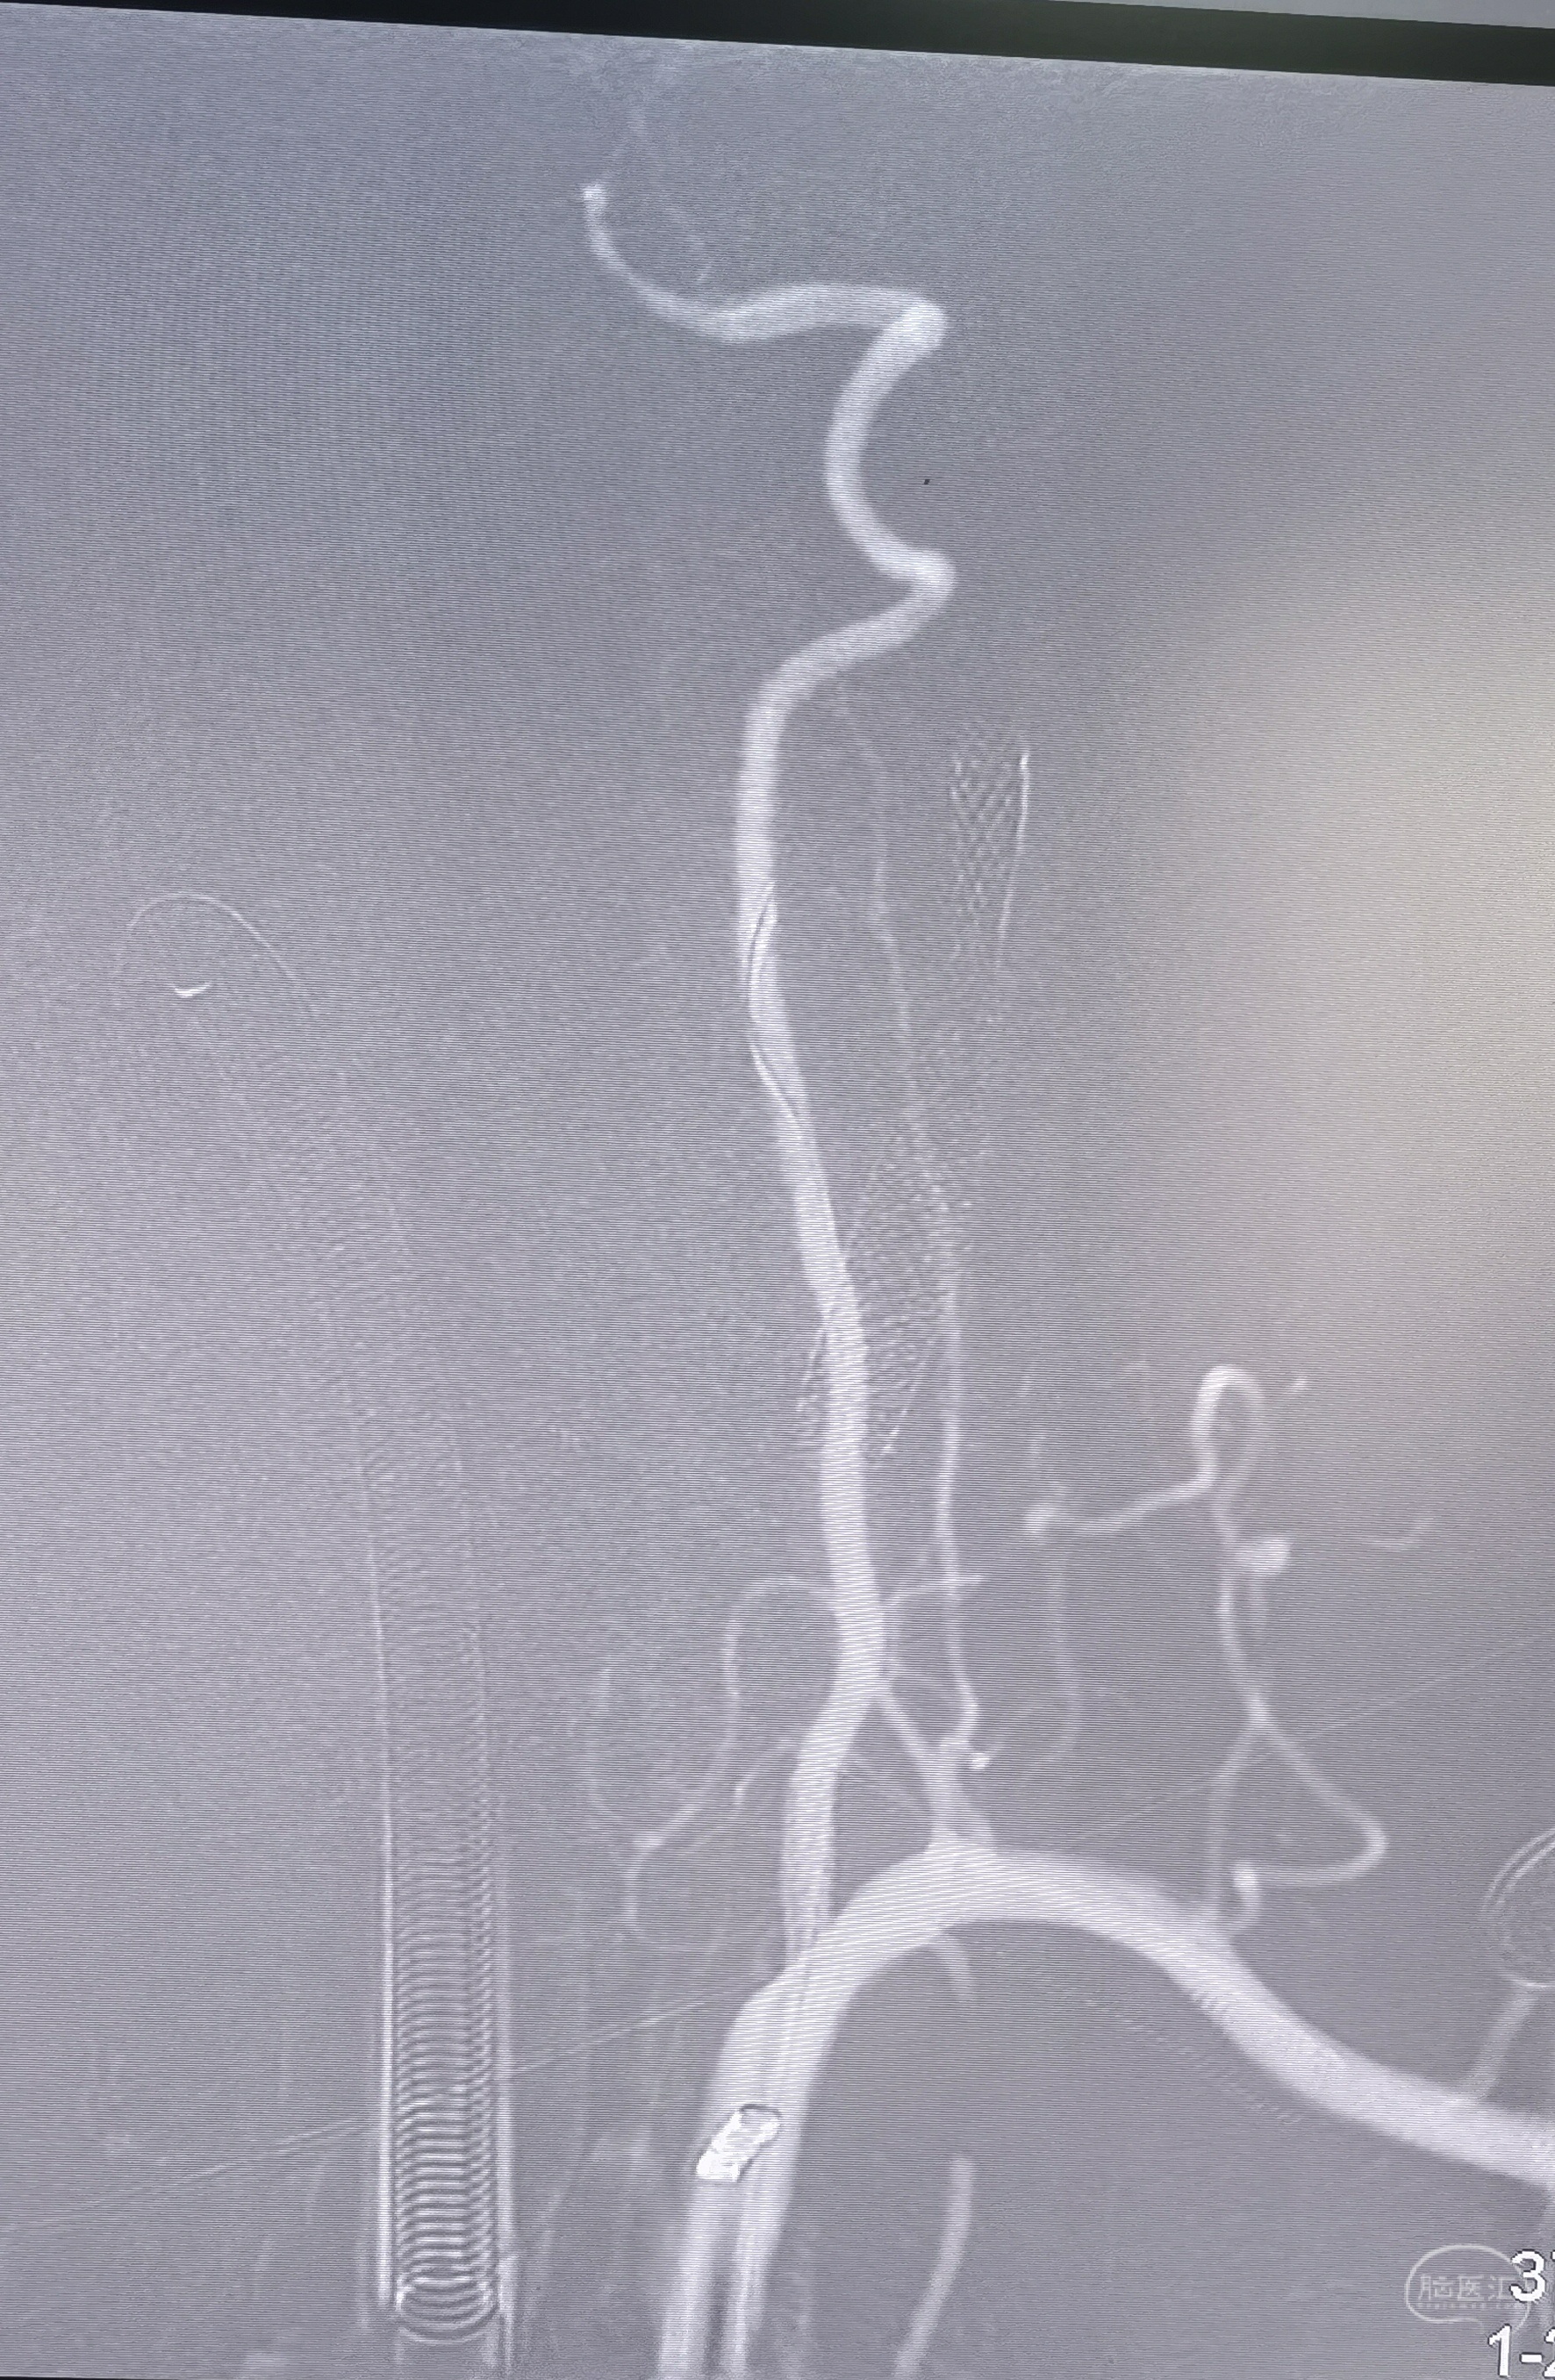

支架置入

支架置入后造影侧位